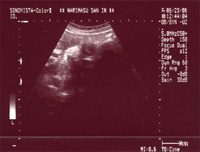

前回の妊婦健診、4D超音波エコーに引き続き、今回も超音波写真の画像をUPしてみます。

前回の健診で、妊娠33週です。

なんだかよく、こんな風に左耳を下にして、こっちを見てくれているような

本日の健診で、妊娠35週です。